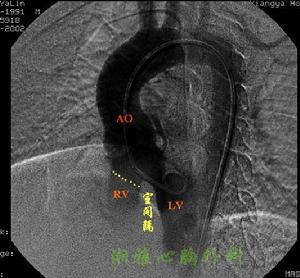

選擇性右心室造影檢查:法樂四聯症病例決定手術治療之前必需作選擇性右心室造影術。於右心室腔內放入心導管注射造影劑,連續X線拍片檢查可顯示肺動脈和主動脈同時顯影和主動脈騎跨程度,與此同時造影劑從右心室經心室間隔缺損進入左心室。造影檢查尚能顯示右心室流出道及/或肺動脈狹窄的部位和程度,了解肺動脈發育情況和測量肺動脈總乾和升主動脈的直徑,計算兩者的比值。

右心室:右心室流入道增大,心室間溝向左移位,心室呈順鍾位鏇轉,左心室轉向後方。右心室壁肥厚,左右心室厚度相近,右心室肉柱增粗,右心室舒張末期容量減少,並因心肌長期缺氧射血功能減弱。

超聲心動圖檢查:切面超聲心動圖檢查對四聯症的診斷很有價值。可直接顯示右心室壁明顯增厚;右心室流出道呈現管狀狹窄或形成第3心室;肺動脈口狹窄;肺動脈口徑比主動脈細小;心室間隔回聲中斷和主動脈前壁右移,騎跨在心室間隔的上方。